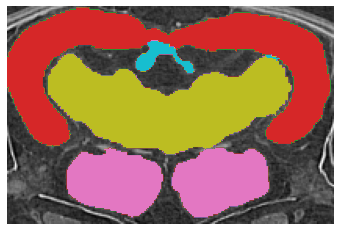

Fig.ย 2: Examples of (a) Input image, (b) ground truth, and segmentation results by (c) the Teacher (Fully Supervised), (d) the Student model by the proposed method.

First, we present a quantitative comparison of the results of the proposed method with the Fully Supervised model as a baseline in Tableย 1. The proposed method clearly outperforms the baseline in both the low and full data regimes. These results demonstrate that our method consistently outperformed the baseline. In addition, the proposed method using only seven labeled volumes provided better performance than the baseline using all available training data volumes, confirming the proposed method can improve the Medaka segmentation performance. Remarkably, our method using only two volumes of the labeled data achieved better results than the Fully Supervised method with 12 labeled volumes. Second, we visually compare the results of the segmentation as shown in Fig.ย 2. We marked the problematic areas of the sample with yellow circles in Fig.ย 2 (c). While the prediction of the proposed method clearly has its own peculiarities of segmentation, the provided result is smoother spatially and closer to the ground truth.